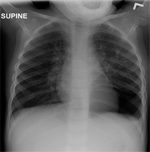

In the emergency department, the patient’s vital signs were stable: he was afebrile (temperature: 36.5oC), not tachypneic (RR: 26/min), and the SaO2 at room air was normal (95%). The chest exam showed decreased breath sounds in left hemithorax. The rest of physical examination was unremarkable.

A chest radiograph was done. After reviewing the findings on that X-ray film, the pulmonary service was consulted.